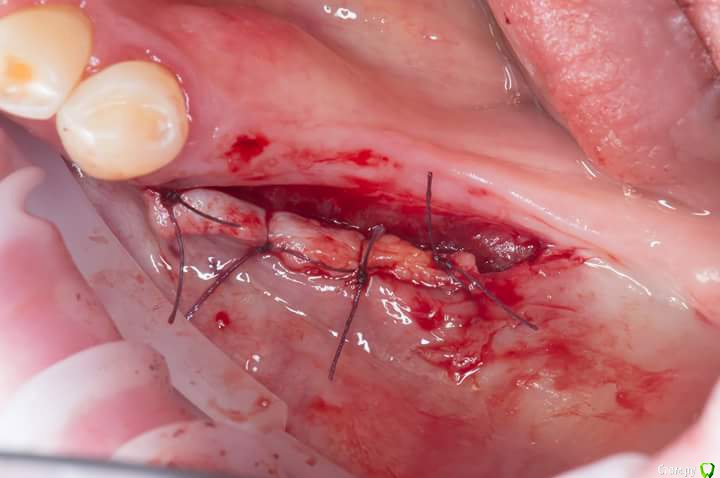

Sampson Опубликовано 3 июля, 2018 Поделиться Опубликовано 3 июля, 2018 1. Забор трансплантата из области 16-17Ушивание2.пластика предверия штрипсой по Урбану3. Установка 2 импланта Adin rpУшивание4.удаление 16. Prf в лунку,поверх губка Альванес. 7 Ссылка на комментарий

Bier Опубликовано 4 июля, 2018 Поделиться Опубликовано 4 июля, 2018 в этом и есть ошибка, штрипса удерживает клетки подвижного эпителия от врастания в зону, где планируется создать КПД. Таким образом пространство между штрипсой и гребнем должно эпителизироваться кератинизированным эпителием. Теперь посмотрите как вы закрепили штрипсу и решает ли она эти задачи. Ссылка на комментарий

Bier Опубликовано 4 июля, 2018 Поделиться Опубликовано 4 июля, 2018 Как мне это исправить тут?Я так понял лоскут ещё ниже сместить??нет, у вас пространство не изолировано. Штрипса должна идти от одного края кератинизированной десны к другому, а у вас только с одного края. 1 Ссылка на комментарий

Sampson Опубликовано 4 июля, 2018 Автор Поделиться Опубликовано 4 июля, 2018 Ааааа, ясно. Спасибо что объяснили. в области 47 там действительно не хватило длинны штирипсы. Ссылка на комментарий

Bier Опубликовано 4 июля, 2018 Поделиться Опубликовано 4 июля, 2018 Ааааа, ясно. Спасибо что объяснили. в области 47 там действительно не хватило длинны штирипсы.нужно было еще кусочек отрезать и довести до конца Ссылка на комментарий